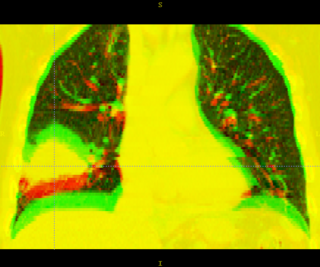

Here is another example, showing the magnitude of tumor regression that can occur during treatment. (Sorry, low resolution image).

Thorax is a special case. Patient images are acquired using 4D-CT, and radiation treatment plan can be evaluated at each breathing phase. The volumes are aligned using deformable registration, and radiation dose from each phase is accumulated into a reference phase (e.g. exhale). This process is called "4D treatment planning."